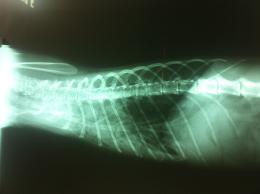

主題: 呼吸困難 嚴重肺炎的貓咪. 申請者姓名: 敏大哥 花色: 申請日期: 2012-05-21 22:45:50 申請者部落格: 申請者臉書網址: 所在縣市/合作醫院: 台北市/詠欣動物醫院 治療費用: 2900元 需求人數: 7人 已結案 (2013-06-27 13:25:09) 報名人員: 咪之寶(已付款)、Alvin Wu(已付款)、DORRY(已付款)、Jelly Lee(已付款)、Jennifer Hu(已付款)、Choco Chen(已付款)、臺北市支持流浪貓絕育計劃協會(代敏大哥替金功實業報名)(已付款)、 候補人員: 蔡雅琳、小舟、 動物病情說明: 平溪張媽媽抓的貓,平溪山上又濕又冷,這隻貓流了幾天的鼻涕,呼吸又很快,好不容易抓了他,送到醫院治療.緊急吸氧氣,打點滴.照x光發現,已經有半個肺在發炎了.給予很強的抗生素,和一天氣霧好幾次.仍舊回天乏術.在治療兩天後就去當天使了.